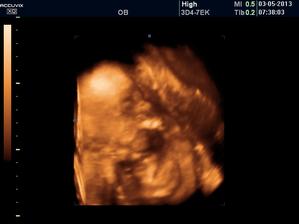

Druhé děťátko

stále nepřichází, ale my věříme, že už to dlouho nebude trvat a přijde mezi nás. těší se na něj Maminka, Tatínek a Bratříček Martínek